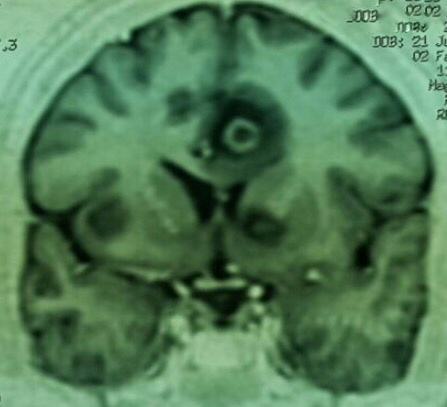

Imagem: Neurotoxoplasmose 8 de fevereiro de 20168 de fevereiro de 2016 ~ infectologia em geral Fonte: enfermaria de Infectologia HRPP Compartilhe isso: Compartilhar no X(abre em nova janela) X Compartilhar no Facebook(abre em nova janela) Facebook Envie um link por e-mail para um amigo(abre em nova janela) E-mail Imprimir(abre em nova janela) Imprimir Curtir Carregando... Relacionado